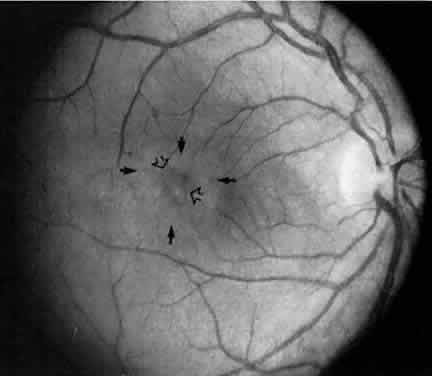

Retinal detachment, vitreous hemorrhage, optic disc swelling, and dragging of the optic disc vessels caused by contraction and neovascularization of cyclitic membranes occur in less than 10% of cases.13,52,53 Periphlebitis has been reported in about 21% of cases.52 Neovascularization of the optic disc53–55 and peripheral retina56 can also occur (Fig. 7). Coat's-like response has been reported in pars plantitis.57 Band keratopathy, glaucoma, and retinoschisis may develop as late sequelae in pars planitis.13

Fig. 7. Pars planitis. Fluorescein angiogram of neovascularization of the optic disc.